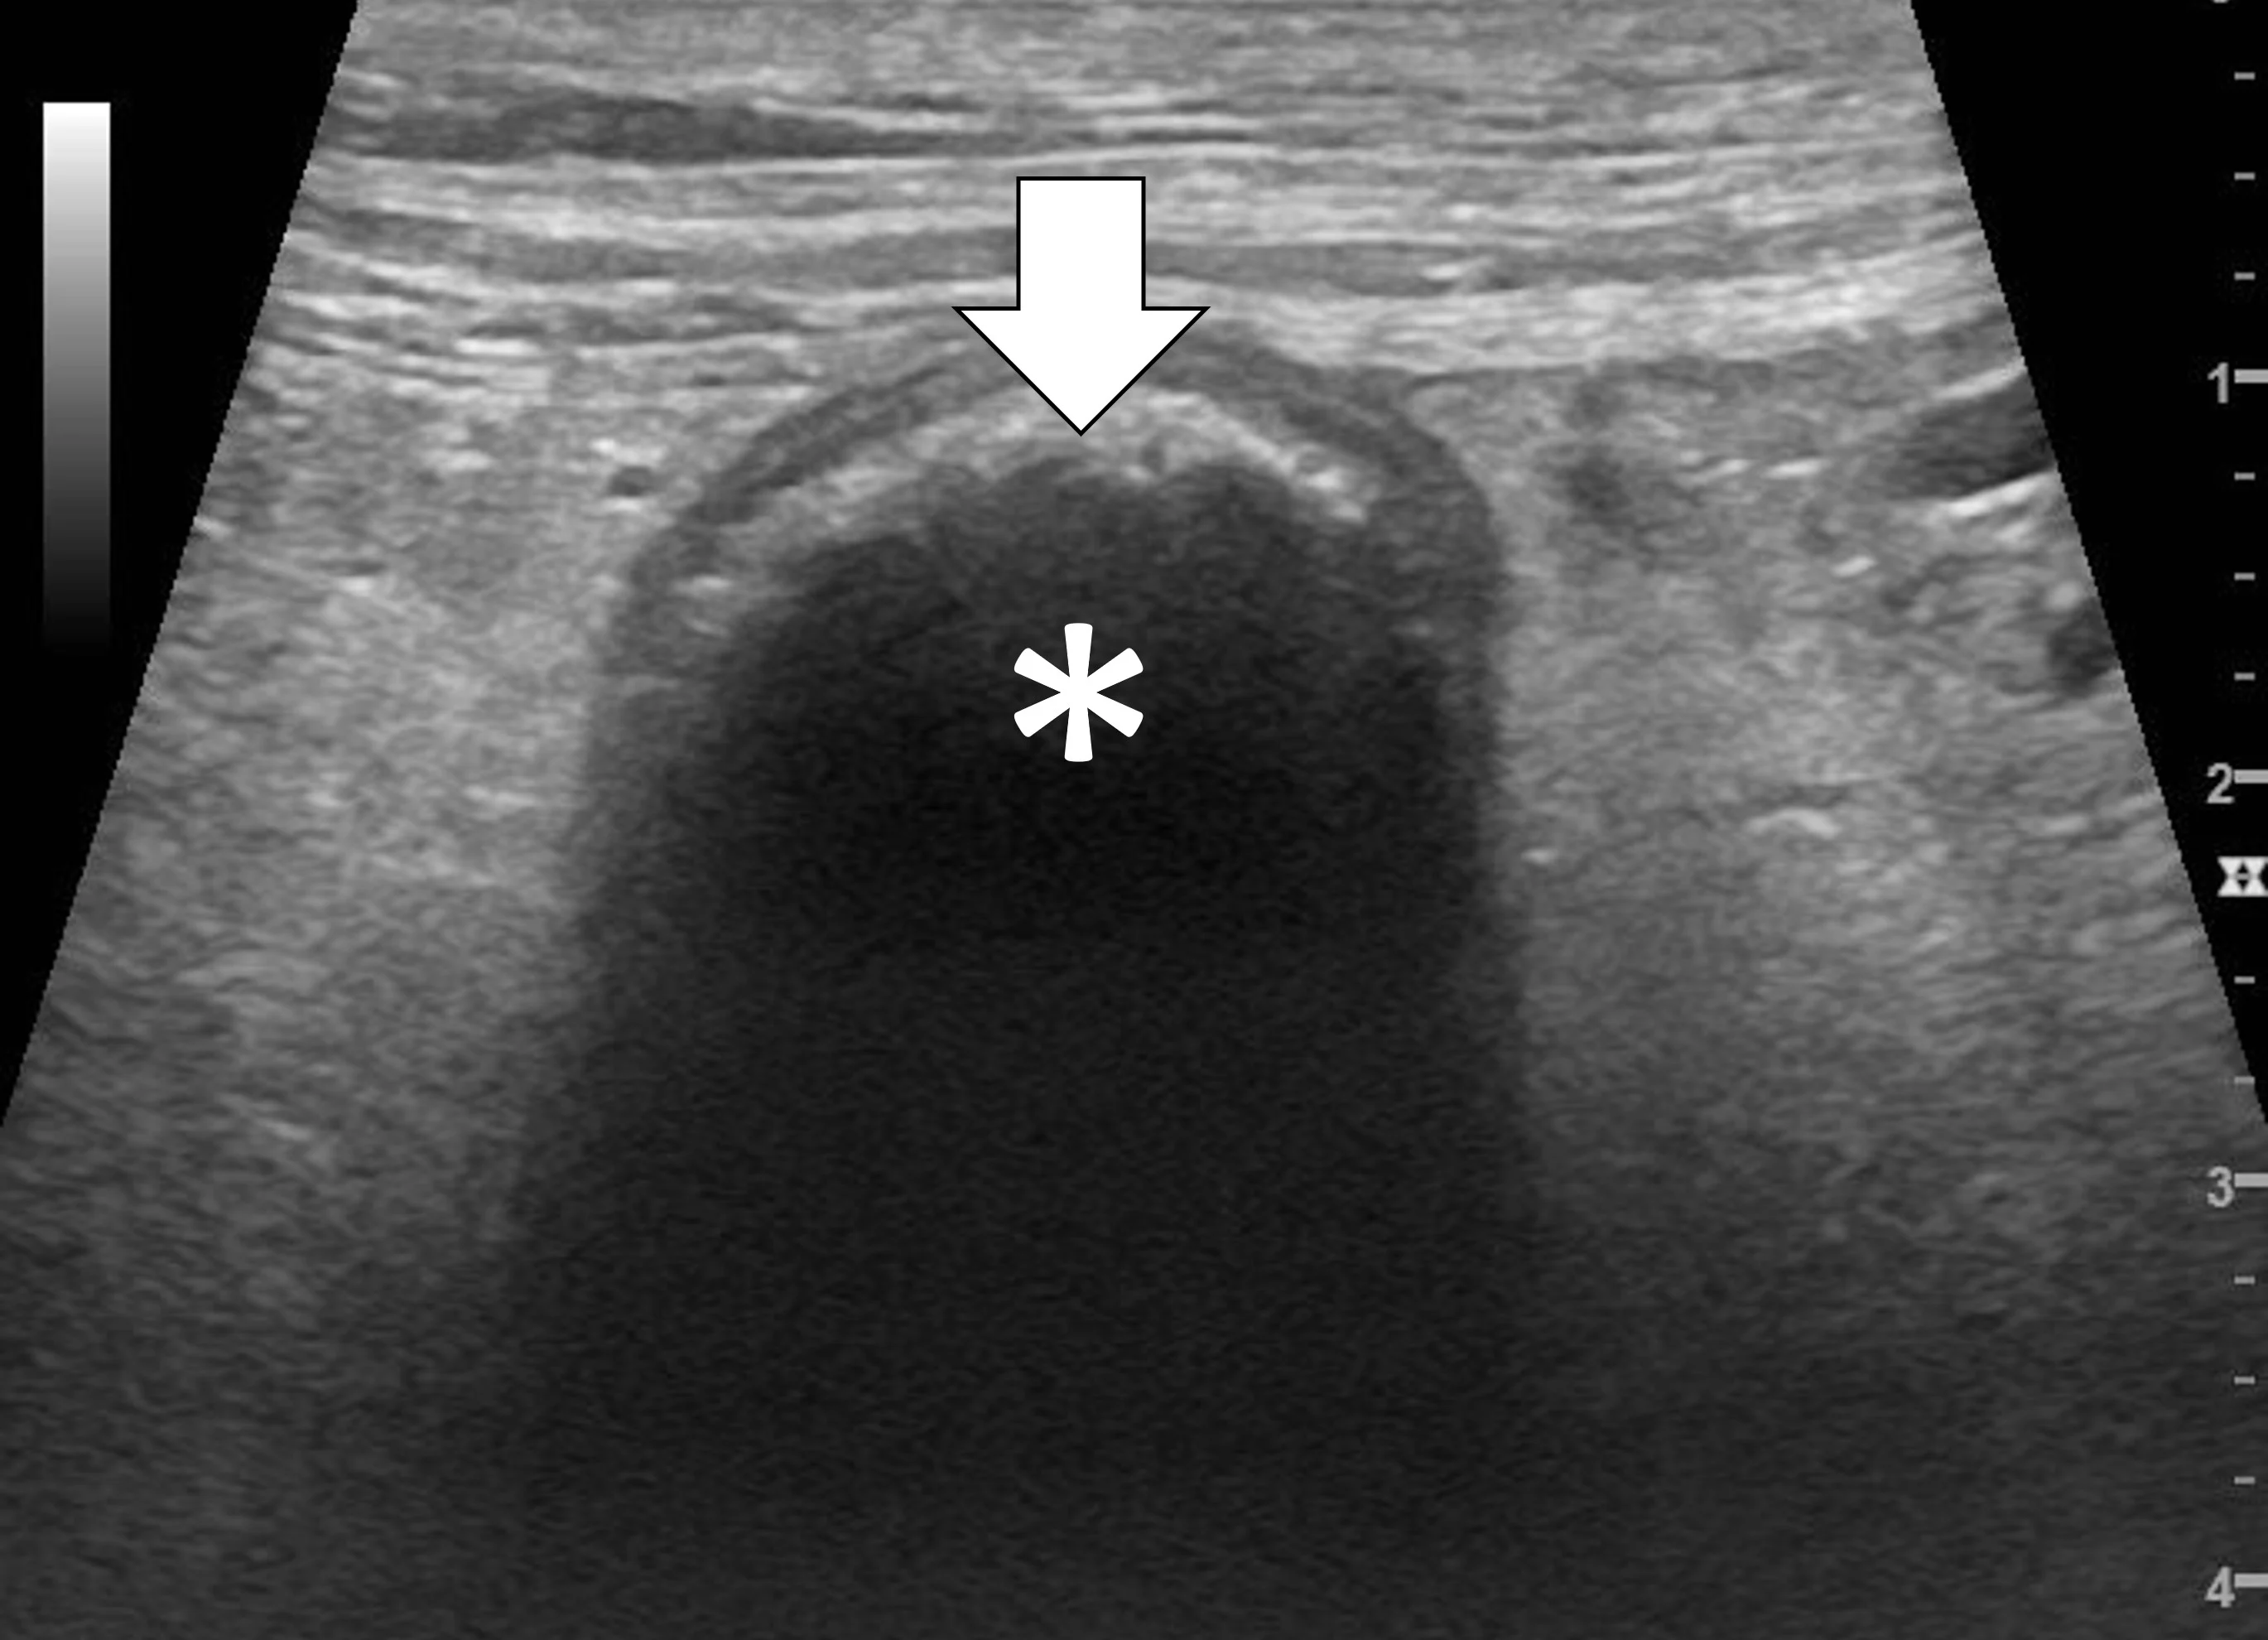

Pyloric outflow obstructions occur when a foreign body lodges in the pyloric outflow tract or the proximal duodenum and can cause variable gastric distention depending on the length of time the obstruction has occurred and whether the patient has recently vomited (Figure 2). Diagnosis of this type of obstruction via ultrasonography requires identification of an intraluminal structure that is causing gastric or proximal duodenal dilation orad to the foreign body.9-12 Foreign bodies are easier to see when surrounded by fluid. Although exceptions are possible, acute complete obstructions typically cause mild to moderate gas dilation, and chronic partial obstructions can cause more moderate to severe dilation, predominately with fluid.

FIGURE 2A

Abdominal ultrasound of a 3-year-old neutered male crossbreed dog with a surgically confirmed mechanical pyloric outflow obstruction. A homogeneously hypoechoic potato (asterisk) is present in the pylorus and completely visible due to its similar acoustic impedance as the surrounding soft tissues. There is transition from gas in the gastric lumen to the foreign body (white arrow). The remainder of the gastric lumen (pound sign) is not visible due to gas (black arrows) causing a hyperechoic surface with reverberation artifact.

Only the gastric wall located in the near field is visible if the stomach is filled with gas. The stomach may need to be evaluated from multiple angles, including subxiphoid, subchondral, right intercostal, and left intercostal. The pylorus shifts craniodorsally and is more difficult to see when the stomach enlarges and the patient is in dorsal recumbency. In these situations, the right intercostal approach can make finding the pylorus and proximal duodenum easier. Evaluating the stomach with the patient in different positions (eg, dorsal recumbency, lateral recumbency, standing) changes the distribution of fluid and gas and may aid in foreign body detection. Gas within the lumen of the stomach masks intraluminal structures; therefore, ultrasonography cannot rule out a gastric foreign body in a gas-dilated stomach.